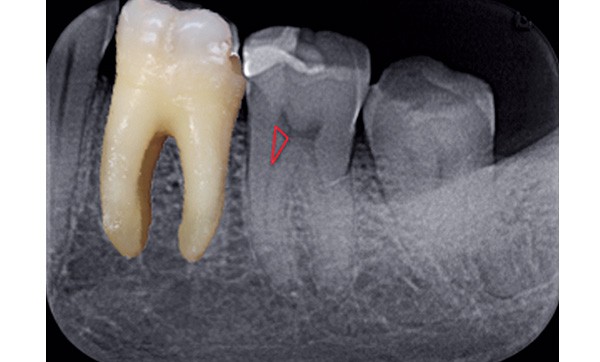

Triangle de Schilder

Les contraintes coronaires, particulièrement représentées par les triangles dentinaires, présents à la jonction entre la chambre et le canal, également appelés triangles de Schilder (fig. 1), s’opposent à la pénétration des instruments et exercent sur ces derniers des forces pouvant, dans le meilleur des cas, freiner leur pénétration apicale et, dans le pire, conduire à la fracture instrumentale.

C’est l’élimination totale des contraintes coronaires qui facilitera l’accès au tiers apical du canal en supprimant le triangle de dentine coronaire qui gène la progression des instruments dans l’axe du canal.

Les évaseurs permettent de supprimer ces triangles internes de dentine. Cette procédure facilite l’instrumentation ultérieure. L’évasement du tiers coronaire du canal est une décision stratégique qui influence toutes les étapes ultérieures de traitement.